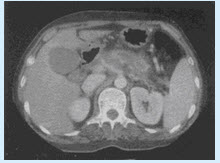

男,56岁。上腹不适3个月,CT检查如图。

(单选题)CT诊断最可能为()

A:胰腺癌

B:胰腺囊肿

C:慢性胰腺炎

D:胰腺假囊肿

E:急性胰腺炎

第2题,共2个问题

(单选题)CT诊断的主要依据是()

A:胰腺肿块+肿块远侧胰管扩张

B:胰腺囊性病灶+肿块远侧胰腺萎缩

C:胰腺肿块+肿块远侧胰腺萎缩

D:胰管扩张+胰腺萎缩

E:胰腺内低密度灶+腹水